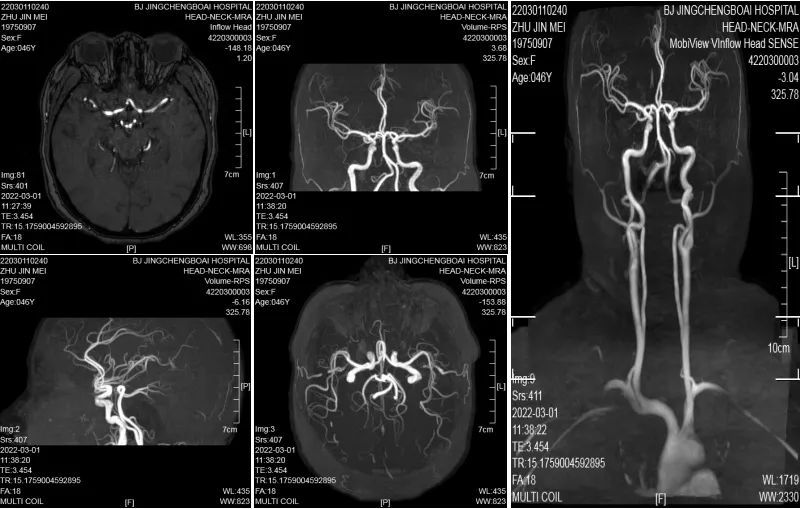

非增强性脑血管成像(MRA)

MRA是一种无创、无辐射、简便经济、精准的脑血管筛查方法,相较脑血管CT三维重建(CTA)和脑血管造影(DSA)则需要注射造影剂,在X射线下辅助完成检查,二者只在进一步确诊脑血管疾病时考虑使用。